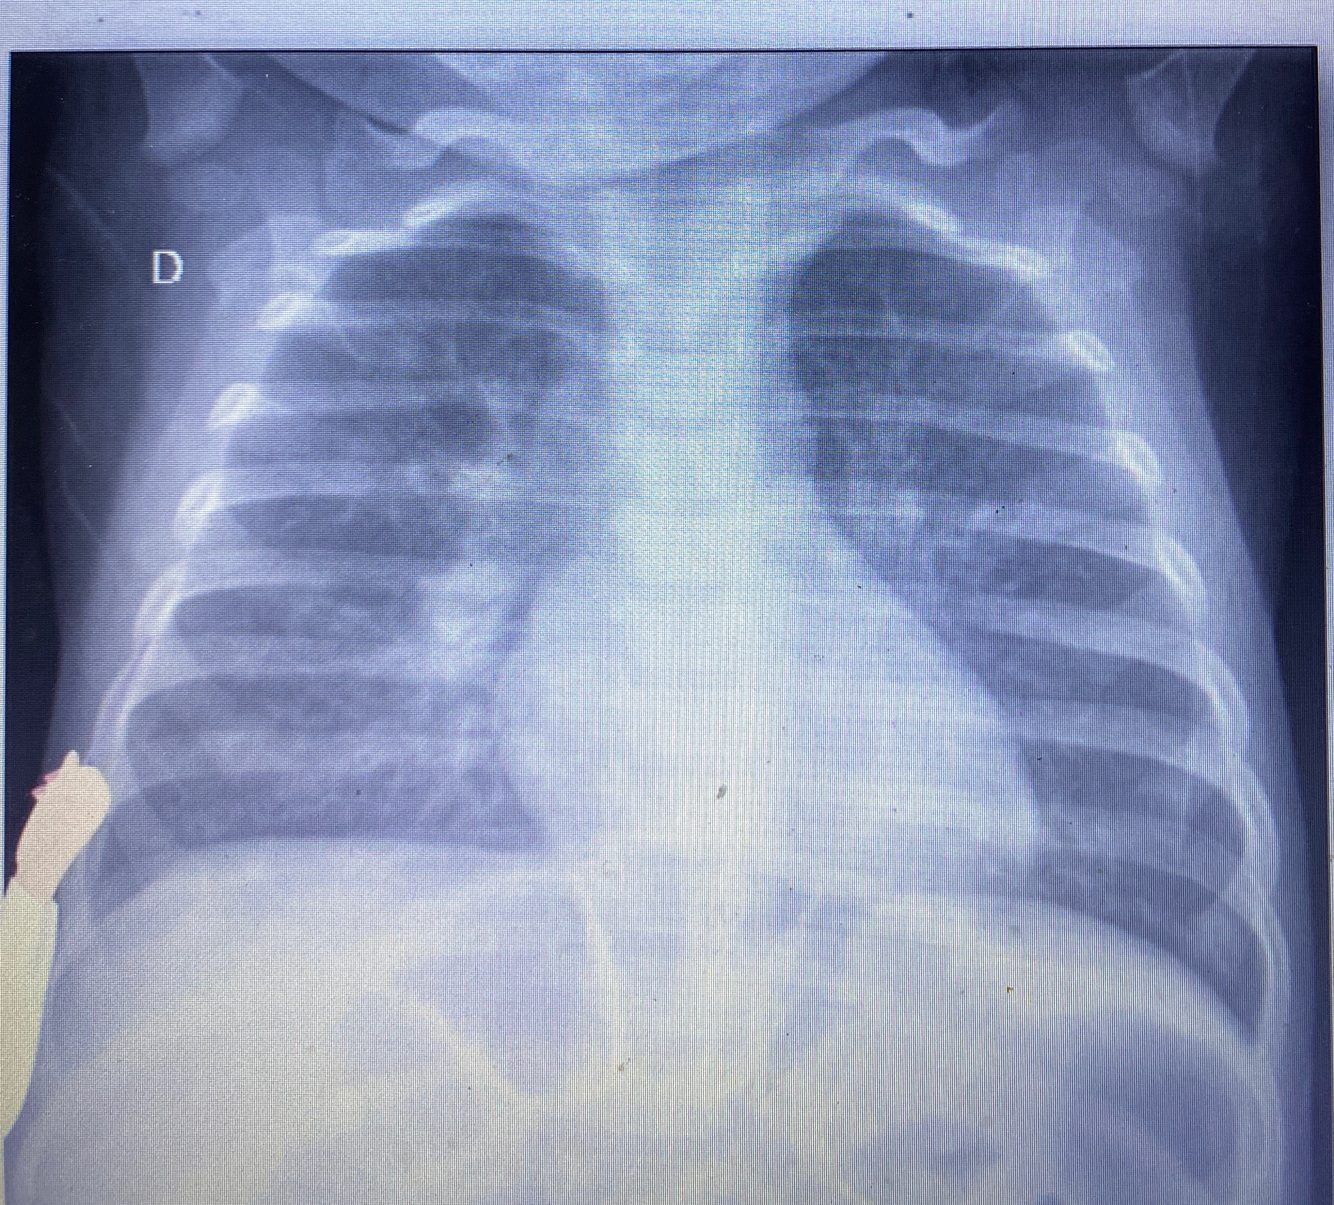

Rx de tórax

Pedir quando desconforto importante internação ver se tem atelectasia

Rx tórax oque ver

Hiperinsuflacao

Espessamento brônquico

Perfil: ar na frente do coração